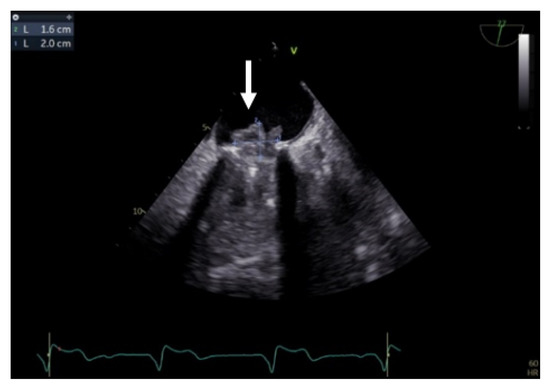

TEE is the gold-standard imaging method for MVT diagnosis, especially when mechanical prosthesis obstruction is caused by thrombosis [1,9,23,24,25,26]. Due to the proximity of the esophagus to the left atrium, the atrial face of any type of mitral prosthesis is accessible (Figure 4, Video S2, Supplementary Material). In the presence of obstructive thrombosis, the mobility of the discs is reduced or even blocked [23,24,27].

Figure 4.

TEE. Thrombus on the atrial side of mechanical mitral prosthesis (arrow).

TEE has a major role in describing the size, mobility, and thrombus extension. It also has the ability to describe whether the thrombus is obstructive or nonobstructive, an essential aspect in the choice of therapeutic management (Figure 5) [1,21,22,25,27,28,29,30,31,32].

Figure 5.

TEE. Obstructive thrombus on the atrial side of mechanical mitral prosthesis (arrow).